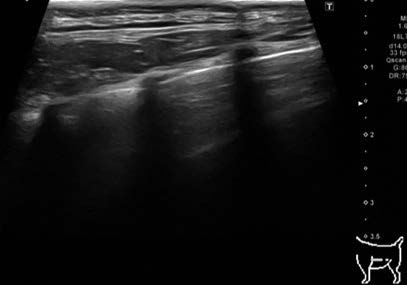

ポイント・オブ・ケア胸部超音波検査:図1 及び2

図1 左側胸壁の肺エコー画像

図1 は症例の左側胸壁からの肺エコー像で,正常な肺で観察されるA ラインを示している.正常であれば高エコー性に描出される肺胸膜ラインの下方に多重反射により形成されたA ラインが認められる.肺水腫であった場合には肺胸膜ラインから垂直方向に減衰せずにA ラインをかき消す高輝度線状アーチファクトであるB ラインが観察されることがある.本症例では両側いずれの領域においてもBラインが認められなかったことや経皮的動脈酸素飽和度が正常であったことから,急性心不全による肺水腫は否定的と判断した.図2 は心膜液貯留と心膜腔内の血餅を疑う構造物を示している.心外膜の外側(心膜腔)に無エコー性の液体貯留が認められることから心膜液貯留と判断できる.さらに一部に血餅を疑うエコー源性のある構造物が存在することから左心房破裂による心膜液貯留と診断することができる.本症例はこれまで心不全に起因していると考えられる症状(頻呼吸,呼吸困難など)を呈しておらず,胸部X 線検査と心臓超音波検査で心拡大の基準(EPIC 基準)を満たしていたことからMMVDACVIM stage B2 と診断された.左心房破裂は心不全を呈したことのないstage B2 でも認められることがある(15 頭中6 頭がstage B2)と報告されているため,心不全の既往がなかったとしても除外できない点に注意する必要がある[1].